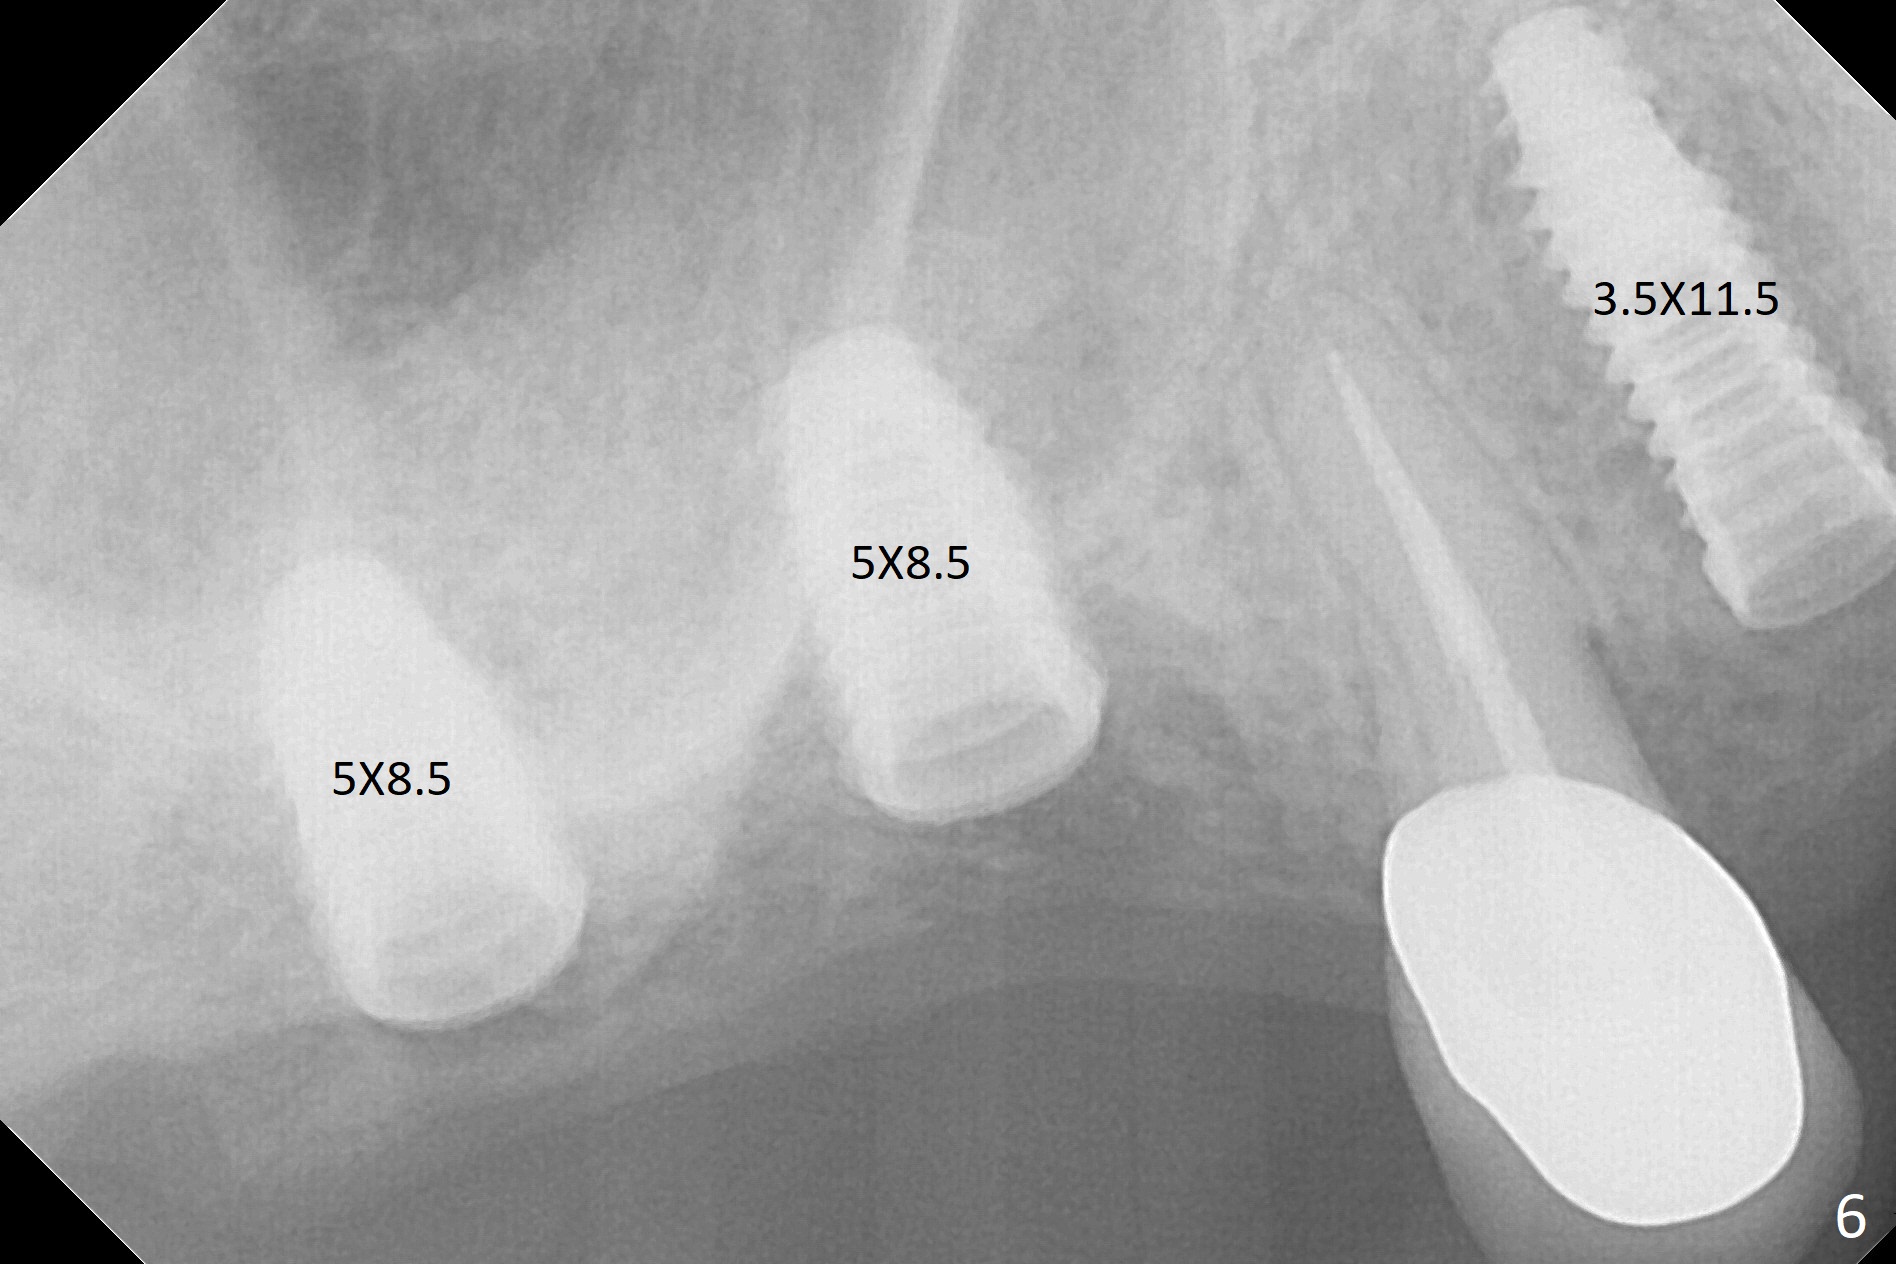

Two of 5x8.5 mm implants are placed at #2 and 3 with sinus lift using water ballooning technique; to avoid invading the neighboring root tips, an intraop PA is taken with a 2.2x11.5 mm drill at #5 (Fig.1). When a 2.5x11.5 mm 1-piece implant is placed at #7, there is 2.4 mm clearance from the impacted tooth (Fig.2). Following 1 mm deeper placement of the 1-piece implant, CT is taken to make sure that the threads are completely covered palatally (Fig.5 P). Interesting is that the sinus membrane is thickened at #2 and 3 (Fig.3 M), as compared to the clear sinus before surgery (Fig.3'). Bone graft is limited in the sinus (Fig.3 arrowheads). The implant at #5 (3.5x11.5 mm) is precisely placed subcrest bucco(B)-palatally (Fig.4). Since the limited field viewed CT does not cover the implant at #2 (Fig.3), immediate postop PA is taken (Fig.6). In fact all of the implants are placed subcrestal, as shown by intraoral X-ray 4 months postop (Fig.7-9). The abutments at #2, 3 and 5 are retorqued (30 Ncm) after crowns' try in and adjustment (Fig.10,11). There is a vertical gap between the implant and abutment at #2 (Fig.11 ^) and a horizontal one at #5 (<). There is apparently no bone loss 1 year 5 months post cementation (Fig.12).